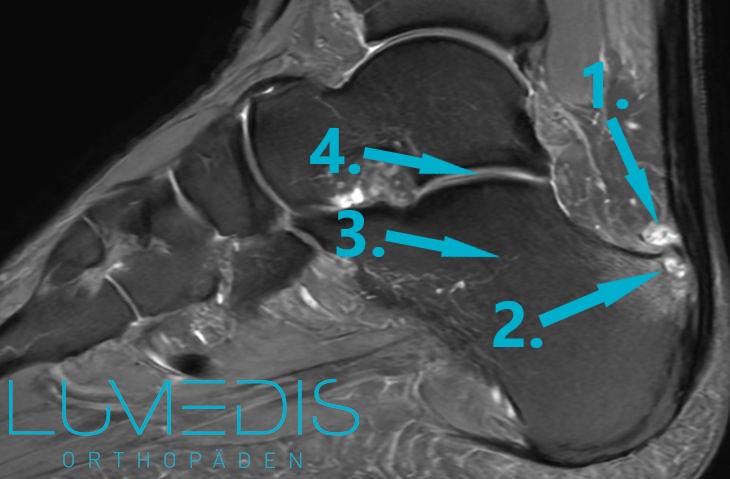

MRT einer Haglundferse rechts:

MRT einer Haglundferse mit Bursitis subachillea

MRT einer Haglundferse seitlich

MRT eines Fußes seitlich (T2)